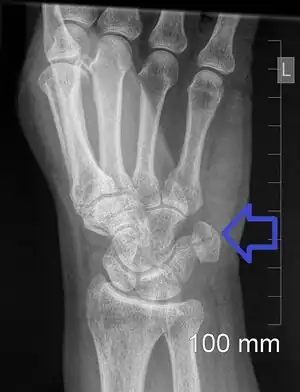

Pisiform fracture

| A pisiform fracture | |

Pisiform fracture is a break of the pisiform bone of the wrist. Symptoms include wrist pain on the side with the little finger.[1][2] They may occur in association with other wrist bone fractures, injury to the ulnar nerve, or ulnar artery.[4][5] Complications may include arthritis and avascular necrosis.[1][3]

The cause is generally the wrist being directly hit, such as may occur during sports, falling on an outstretched hand, or from repetitive injuries.[1][5] It may also occur as an avulsion fracture.[1] Types are transverse, parasagittal, comminuted, and pisiform-triquetral impaction.[1] Diagnosis is generally by X-rays, though specific views may be required.[1] CT scan may be bone to rule out other injuries.[6]

The fracture may be better see on a specific wrist X-ray known as a carpal tunnel view or a lateral view with 30 degrees of supination.[4]